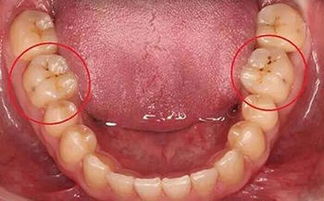

3、佩戴保護措施:如牙冠、嵌體,根管治療后患者牙齒較脆,易裂,建議佩戴保護措施,避免牙齒裂開。若患牙裂開,在目前的醫(yī)療技術下,只能選擇拔除患牙。